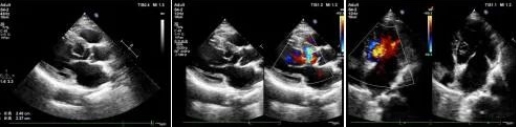

市中心医院超声科成功诊断一名罕见先心脏病患者

3月9日,乐鱼在线登录入口超声科主治医师魏锦为患者进行超声动态检查。

据了解,患者李某,男,63岁,因突发胸闷气短就诊于乐鱼在线登录入口心血管内科门诊。门诊医生接诊进行相关查体后,怀疑患者心脏突发急症,心电图T波异常,遂建议行超声心动图检查。

在超声动态影像检查下主治医师魏锦发现主动脉瓣环下约10mm处见线样强回声突入左室腔,为给出明确诊断,超声科心脏血管组医师共同对患者进行诊断,凭借丰富的实践经验,最终诊断结果为“左室囊袋状结构,考虑内膜撕脱”,提示患有“先天性心脏病主动脉左冠窦窦瘤形成伴破裂入左室”这种罕见病症。乐鱼在线登录入口超声科在第一时间为患者制定最佳治疗方案提供了保障。

患者遂转往空军军医大学西京医院手术治疗。术中实际情况也证实了术前的超声诊断。

“这种疾病非常罕见,诊断过程中想到这个病很关键!”西京医院相关领域专家对乐鱼在线登录入口超声诊断水平高度的认可,也展现我院超声诊断水平有了飞跃式的提高。